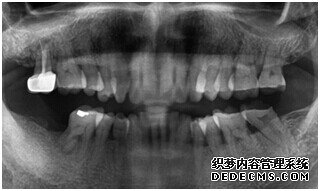

牙齿拍片初步检查

刘女士牙齿拍片初步检查

专家诊断:最后一颗牙齿通常不易清洁,且牙齿长了蛀牙之后也不容易发现,很多人就跟 刘女士一样发现的时候就已经是蛀牙中期甚至是后期了,这个时候一定要尽早治疗。不然和刘女士一样必须拔牙是非常可惜的。

由CT片检查来看,刘女士口腔健康环境还是很好的,牙槽骨也适合种植牙的条件,而且由我们最后一颗牙是非常重要的,经过专家的建议和详细解释了原因之后,刘女士选择了美国百康种植牙。